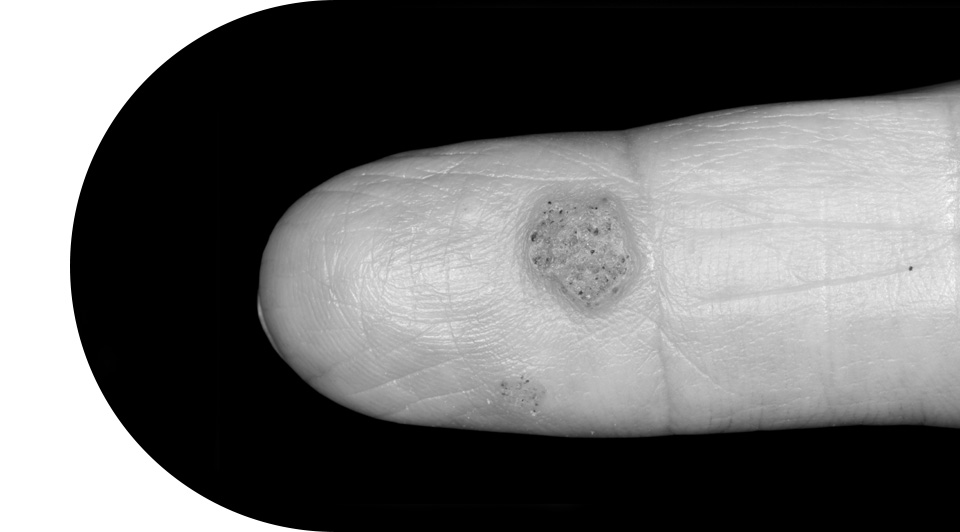

번지기 쉬운 사마귀/티눈

사마귀는 유두종 바이러스(HPV)에 의해 나타나며

전염성이 있어 빠른 치료가 필요합니다.

티눈은 물리적인 자극 마찰로 발생하는 질환으로

심지가 있어 압력이 가해지면 통증을 유발합니다.

사마귀/티눈치료대상

크기가 크고 단단한 경우

병변을 오랫동안 방치하여 제거하기 힘든 경우

약이나 밴드 등을 통한 제거가 어려운 경우

미처 뿌리까지 제대로 제거하지 못한 경우